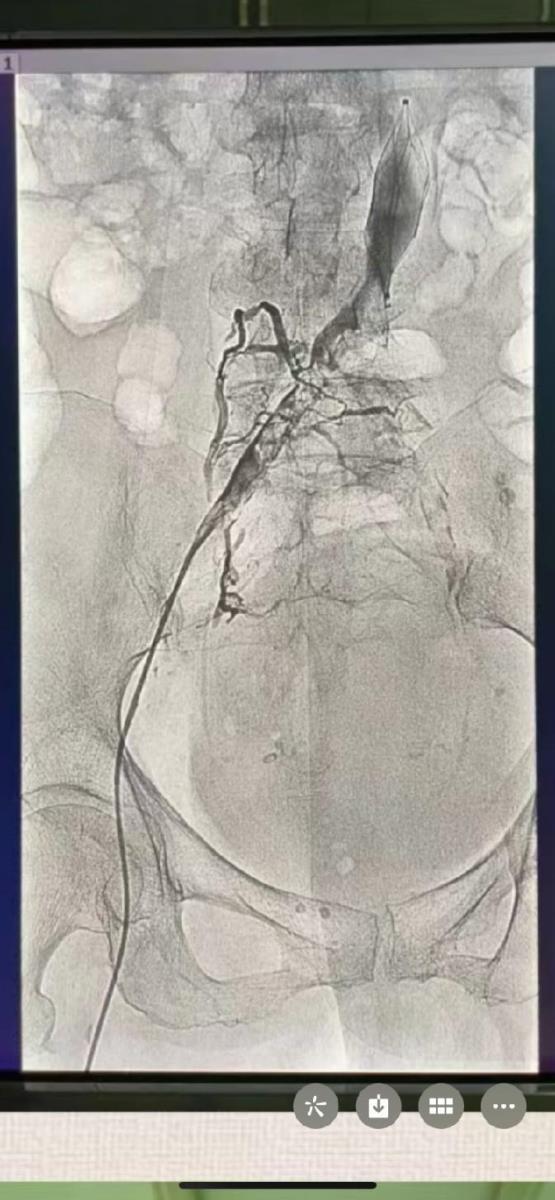

完善检查行下腔静脉造影滤器植入+左腘静脉彩超引导穿刺。

余启松主任及王承医生决定行血栓抽吸术,髂静脉狭窄球囊扩张术。